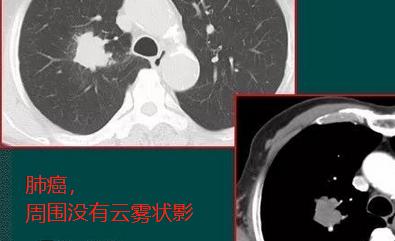

也许读者朋友对上面的文字内容不够理解,我们再看几张类似的肺癌的肿块图:

分叶状肿块,支气管截断,周围没有云雾状影,病理为大细胞癌

上面3个病例都是确诊的肺癌,第1和第3例还有手术切除的机会,第2例是转移性癌,没有手术机会了,只能保守治疗。